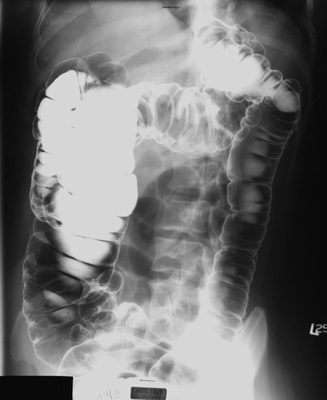

- RPO view of colon to include splenic flexure and descending colon -

14" x 17";

cassette

- LPO view of colon to include hepatic

flexure and ascending colon - 14" x 17"